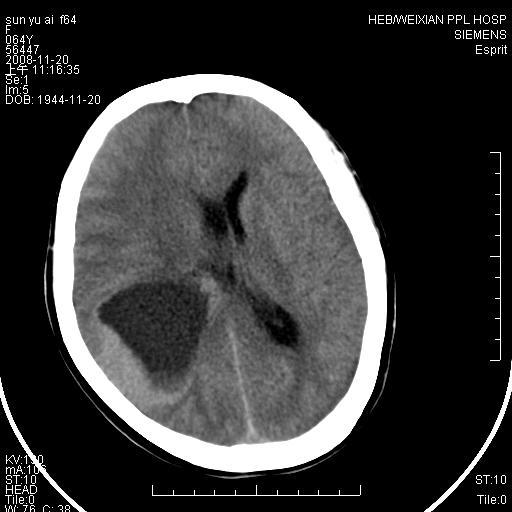

影像表现:侧脑室三角区附近可见以形态不规则的囊实性肿块,其中以囊性成分为主,实性成分为辅,边缘清晰,未见水肿,轻度占位效应,脉络丛钙化向内上移位,右侧脑室轻度扩大(也许体位所致),

影像诊断:1室管膜瘤

2胆脂瘤 建议增强吧

1、右侧大脑半球囊实性占位病变,以囊性变为主,实性部分位于病变外后侧,周围无明显水肿,占位征象明显。

2、多考虑胶质瘤可能性大。

右颞顶叶囊实性占位,有壁结节。考虑间变性胶质瘤可能性大,建议增强进一步检查。

右颞顶叶囊实性占位,有壁结节,考虑胶质瘤可能性大,建议增强进一步检查。